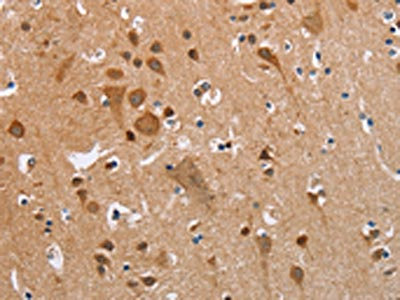

The image on the left is immunohistochemistry of paraffin-embedded Human brain tissue using CSB-PA297945(KRT13 Antibody) at dilution 1/35, on the right is treated with fusion protein. (Original magnification: ×200)